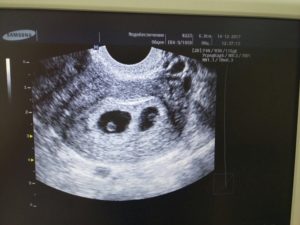

В этот же период начинается рост плаценты – уникального органа, обеспечивающего защиту и питание плода. Из трофобласта и эктодермы образуются амнион и хорион. Амниотическая полость заполняется околоплодными водами, а хорион начинает активно продуцировать ХГЧ. Размеры эмбриона достигают значения в 4 мм и его уже можно увидеть на УЗИ.

После проведения анализа на содержание в крови хорионического гонадотропина женщина уже может знать, что она носит в себе новую жизнь. Спустя 3 недели беременности, что происходит с плодом – можно разглядеть с помощью ультразвукового исследования.

На этом этапе эмбрион представляет собой крошечный шар с едва различимыми головным и хвостовым концами, окруженный плодным яйцом. УЗИ-диагностика на ранних сроках беременности проводится двумя способами:

• Трансвагинальным, при котором непосредственно во влагалище вводится небольшой датчик, излучающий ультразвуковые волны. Именно такая процедура позволяет наиболее детально рассмотреть состояние матки и плодного яйца в ней. Для подготовки к сканированию не требуется особых приготовлений, кроме исключения из рациона за несколько дней до УЗИ продуктов, провоцирующих повышенное газообразование, а также опустошить кишечник и мочевой пузырь непосредственно перед процедурой;

• Трансабдоминальным методом рекомендуется пользоваться на больших сроках. Такое обследование не требует никакой подготовки, но и является менее подробным из-за большего количества структур на пути ультразвука.

Именно УЗИ на третьей неделе после введения эмбрионов является методом, позволяющим достоверно определить наличие беременности, так как ЭКО, к сожалению, не всегда может гарантировать удачный результат.

Кроме того с помощью ультразвукового сканирования можно увидеть:

• Количество жизнеспособных эмбрионов в матке;

• Место расположения плодного яйца;

• Изменения в яичниках.

Первое УЗИ является необычайно важным для исключения серьезных патологий в виде внематочной беременности, остановки развития плода, определения многоплодной беременности и необходимости дальнейшего проведения или коррекции поддерживающей терапии.